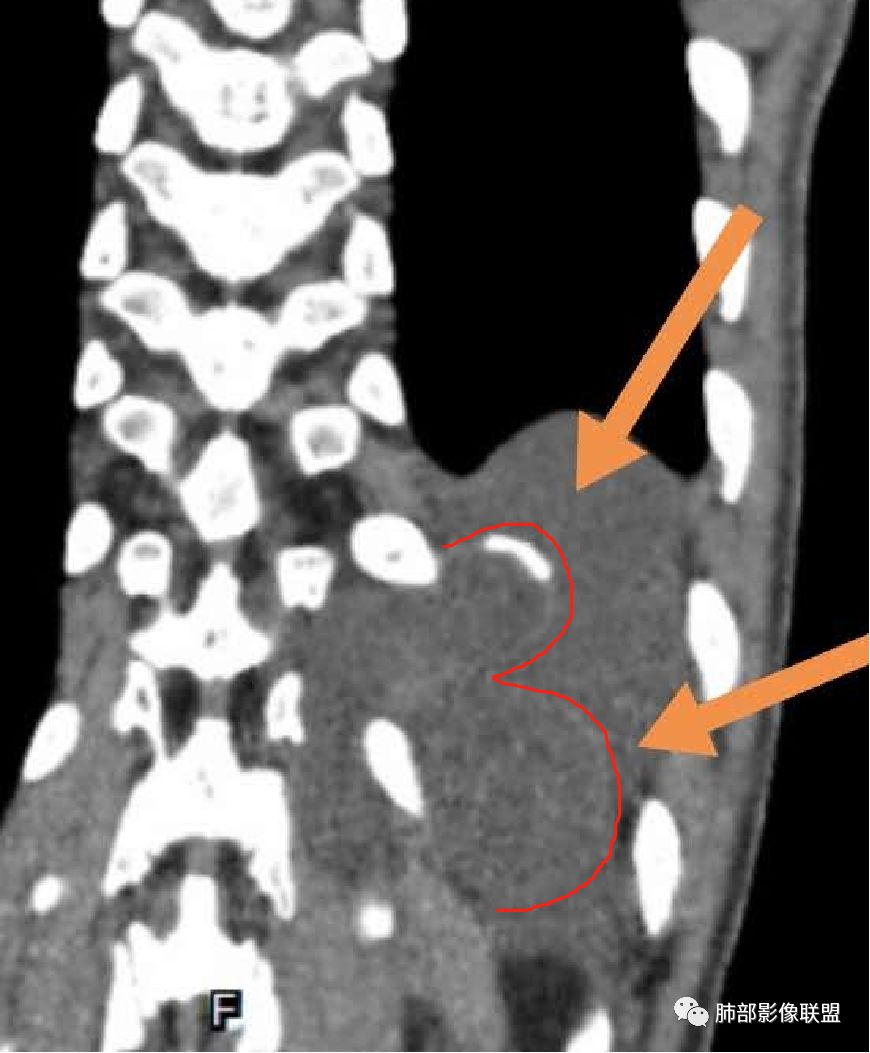

现在我们重新回顾性分析这个病例的影像特点:

1.含有少量脂肪密度成分,位于病灶中央区,应当是病灶内的一部分,或者说至少这部分不是被包绕卷入的。常见病灶内含有脂肪组织的肿瘤:多种脂肪瘤、脂肪肉瘤、畸胎瘤、其他肿瘤伴脂肪化生或分化。

2.病灶中间弧形稍高密度影,提示纤维组织可能,而且很有张力并呈分叶状,伴弧形钙化,提示这个倾向于病灶的包膜。

我们知道囊性成熟畸胎瘤中外胚层来源的上皮组织有腺体,有脂质,分泌粘液,囊性病灶有张力,囊壁也可以有弧形钙化,但易脂质上浮呈液平面,囊性畸胎瘤较少见如此明显的分叶,更少见在不同组织区间漫延串扰。

3.部位深在且四处侵入,含脂质较少或整体密度高于脂肪的脂肪类肿瘤应当想到脂肪肉瘤的可能性,因为它可以粘液样变。

但本例病灶边界清楚,有一定规模而相邻骨质未见异常,提示整体倾向良性或者恶性程度不高。

包膜钙化往往提示病灶存在时间较长且较为固定。